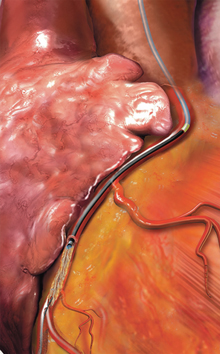

カテーテル的左心耳閉鎖術(WATCHMAN™)

心房細動があると脳梗塞のリスクが高まります。そのため抗凝固薬(血液サラサラ)服用の必要がありますが、それにより出血のリスクも高まります。つまり抗凝固薬による出血リスクが高く(胃や腸からの出血、脳出血、眼底出血を起こしたことがある方なども含む)心房細動がある方が治療対象となります。WATCHMAN™は心房内の左心耳に装置を留置し、心房内で血栓が形成されるのを防ぐ役割を果たします。1回の手技で生涯の脳卒中リスクを低減することが可能です。